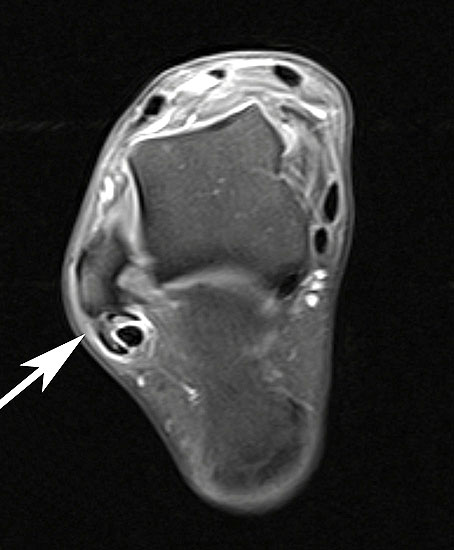

Unterbrechung des Retinakulums als indirektes Zeichen einer traumatischen Peronealsehnenluxation im MRT.

Abbildung 6

Neben der klinischen Untersuchung besitzt in der Diagnostik von Sehnenpathologie das MRT mit Kontrastmittel einen hohen Stellenwert 8910. Kontrastmittelaufnahme in die Sehne ist immer als Hinweis auf einen Riss zu werten. Weiterhin ist Flüssigkeit im Sehnengleitlager oder die Aufnahme von Kontrastmittel in das Sehnengleitgewebe ein indirektes Zeichen einer Sehnenpathologie.

Springt die Sehne spontan in ihr Gleitlager zurück, ist das MRT ohne Kontrastmittel häufig unauffällig, mit Kontrastmittel ist regelhaft eine Signalveränderung des Retinakulums erkennbar. Kommt es nach einem Trauma spontan zu einer Reposition der Peronealsehnen, so kann eine konservative Behandlung mit sechswöchiger Ruhigstellung des Sprunggelenks im Unterschenkelgips versucht werden. In etwa 50% der Fälle kann so eine narbige Heilung des Retinakulums erreicht werden 25, in den restlichen Fällen bleibt eine Instabilität bestehen. Kommt es zu keiner spontanen Reposition der Sehnen, besteht primär die Indikation zur operativen Rekonstruktion. Eine chronische Instabilität ist durch konservative Maßnahmen nicht zu beeinflussen. Die Indikation zur operativen Stabilisierung ergibt sich aus dem Leidensdruck.